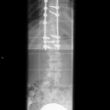

Scoliose